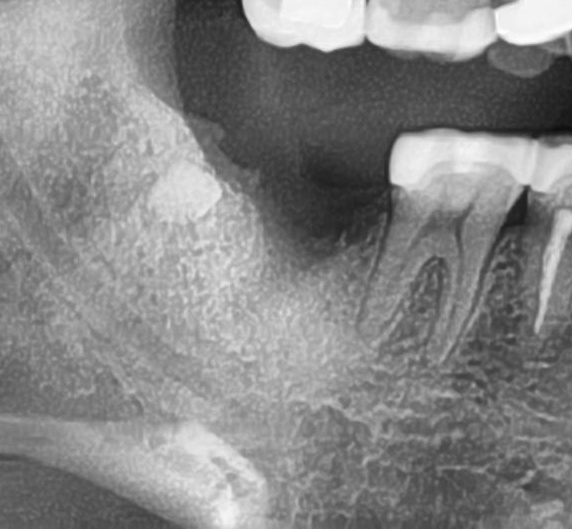

今回の患者様はインプラント植立を希望され、右下7番目の植立が決まりました。

ドリルの先端を細い物から徐々に大きい物に変えながら、植立するインプラント体のネジの部分を除いた胴の部分の太さに合わせた大きさの穴を開けていきます。

開けた穴に、専用道具を使ってネジを締めるように長さ2センチ程のインプラントを骨に埋め込んでいきます。

しっかりとインプラント埋め込まれた後は、動揺がないか、噛んだ時に当たらないかなどを確認して、最後にパノラマ写真を撮影して今回のオペは終了となりました。